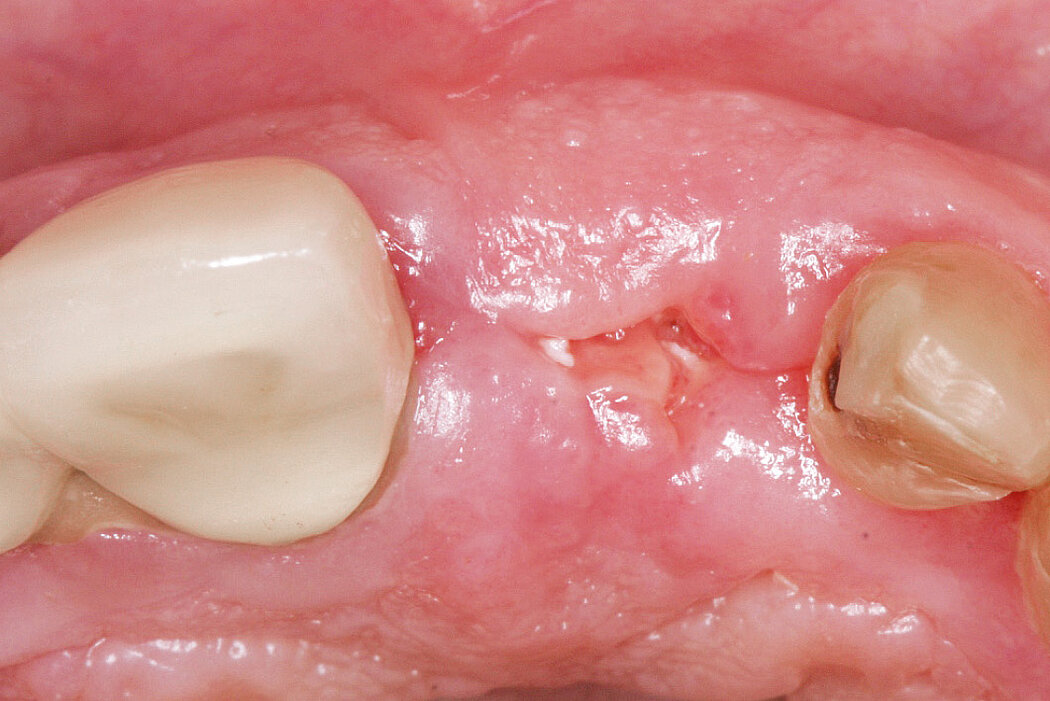

拔牙窝缺损的牙槽嵴保存(开放性愈合)

病例来自 Dr. Célia Coutinho Alves

葡萄牙,波尔图

临床挑战

在可行的情况下,我们更倾向于保存骨而非后续进行骨重建,对于前牙尤其如此。

目的/方法

保持美学区的硬组织和软组织轮廓。单牙缺失的延迟种植

结论

使用盖氏生物材料可防止重度牙槽嵴吸收。植入种植体时,使用盖氏生物材料和结缔组织移植物进行额外塑形,获得了持久的良好效果。

拔牙前与拔牙后11个月的比较